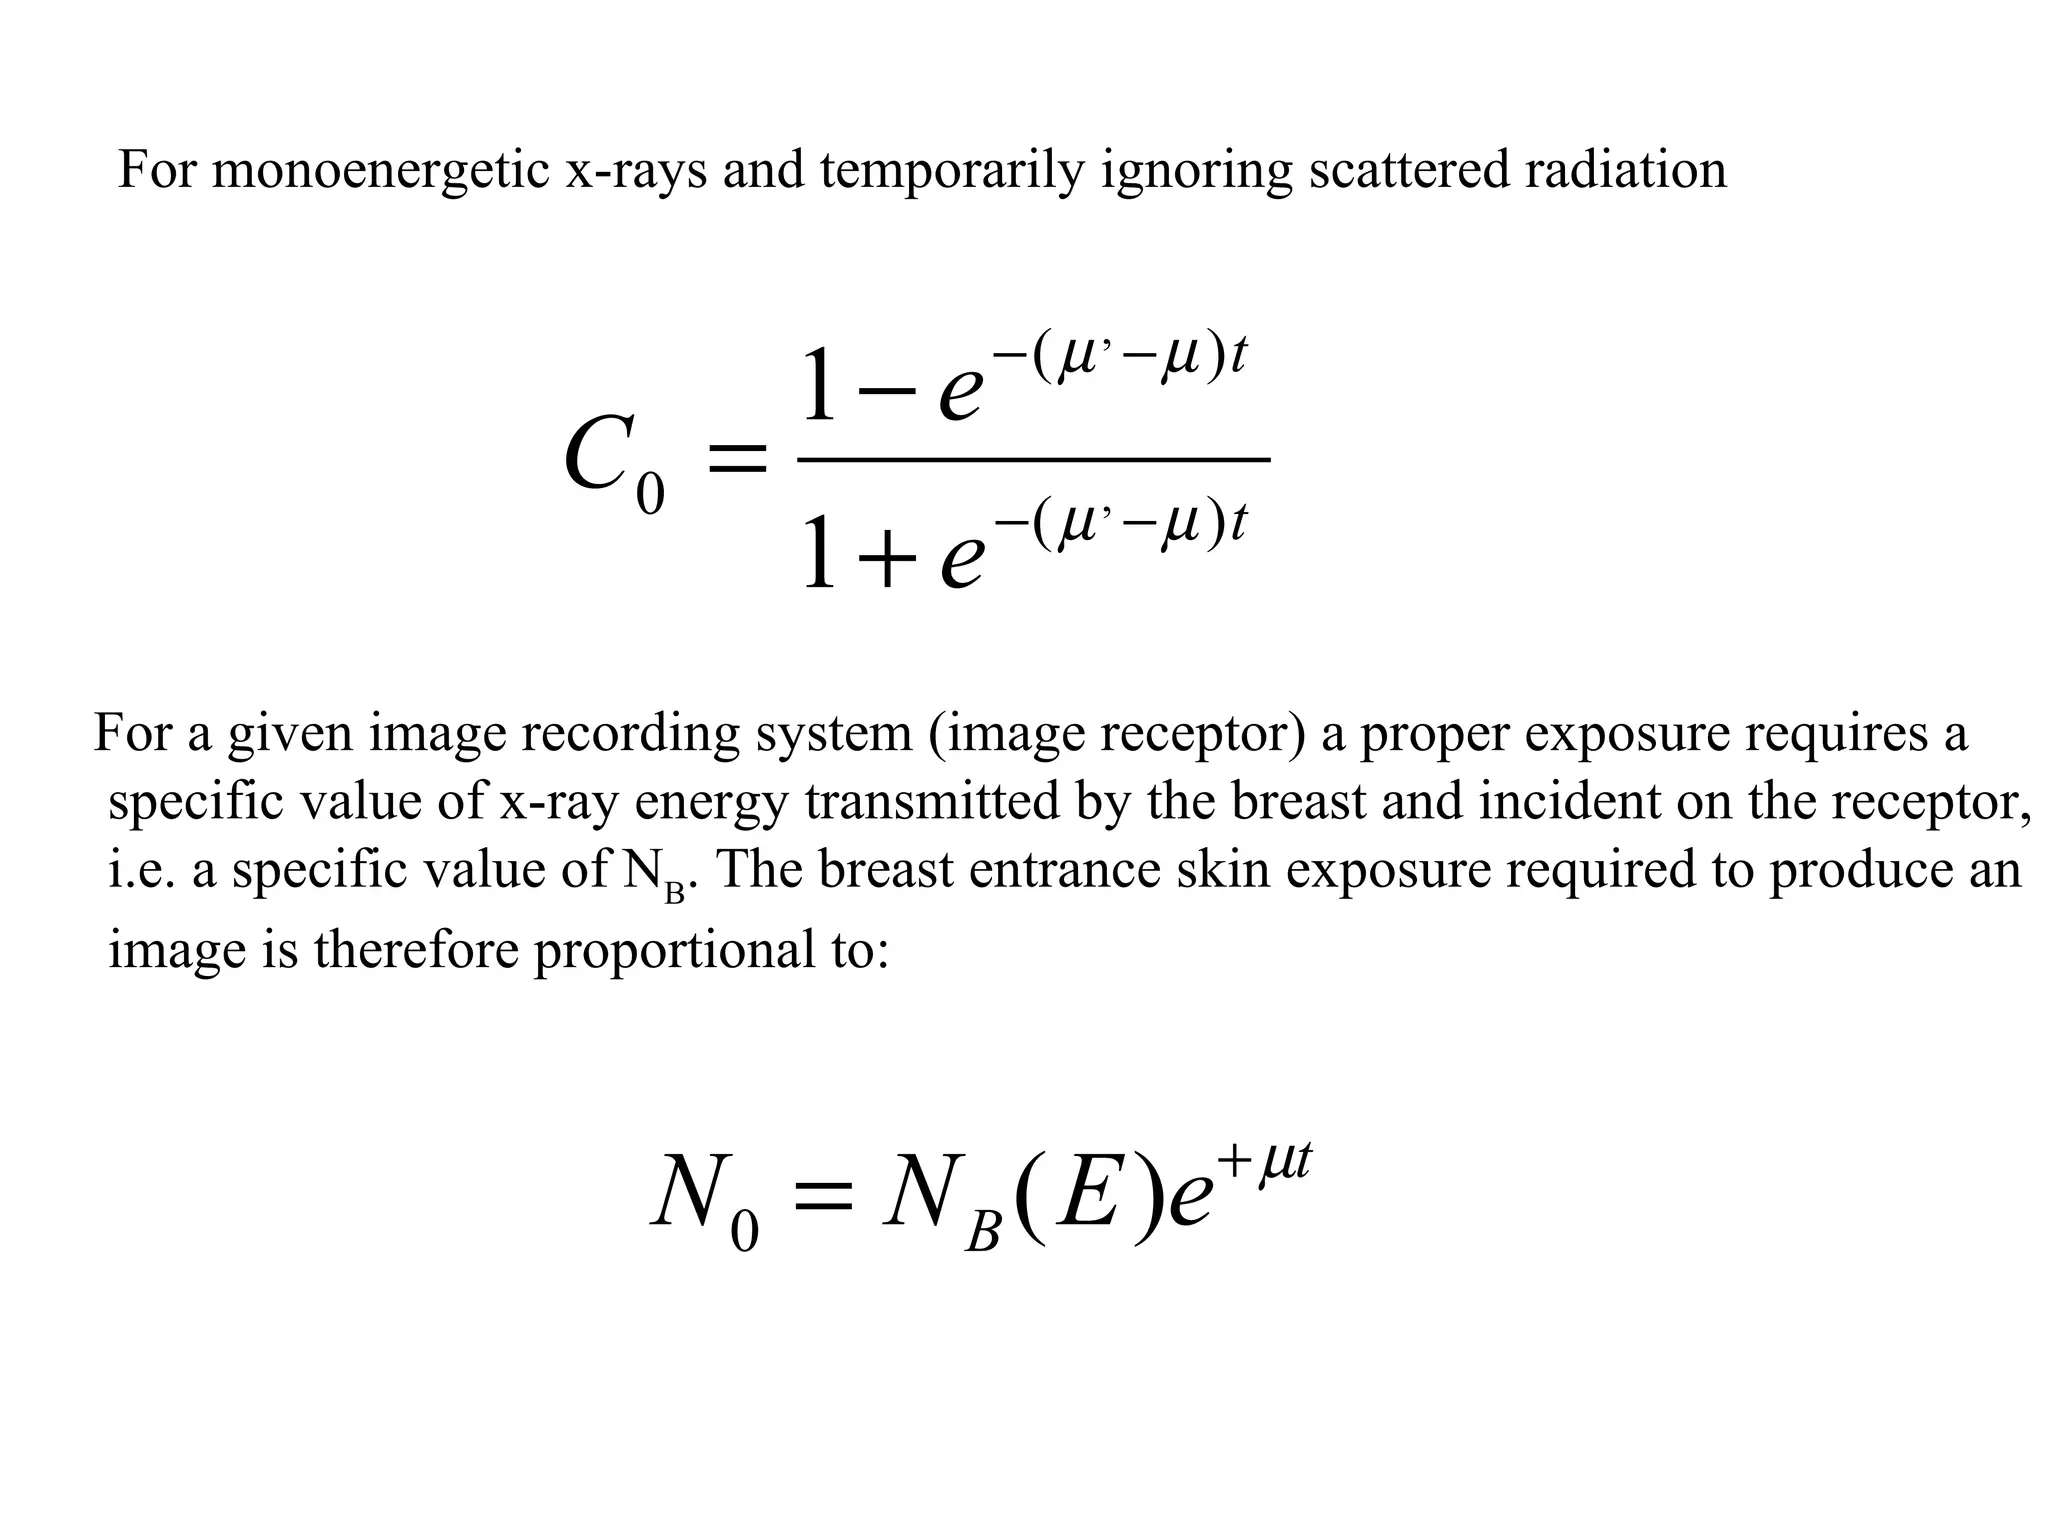

The document discusses various medical imaging modalities including x-rays, computed tomography (CT), and digital mammography. It describes the basic principles and historical development of these technologies, how images are formed, and what types of anatomical features and abnormalities they can detect. Key advances include the development of digital systems that allow image manipulation and remote consultation. While promising, digital mammography still faces challenges around resolution and cost.